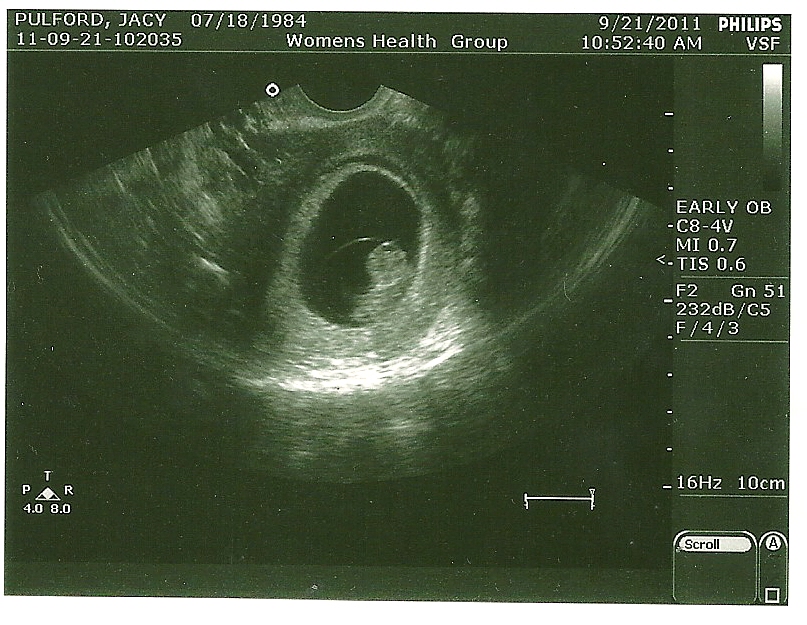

Hi!!! I'm Baby Pulford and I'm only 9 weeks old.

My head is a little big but my little paddles are growing fingers and I'm wiggling like a worm.